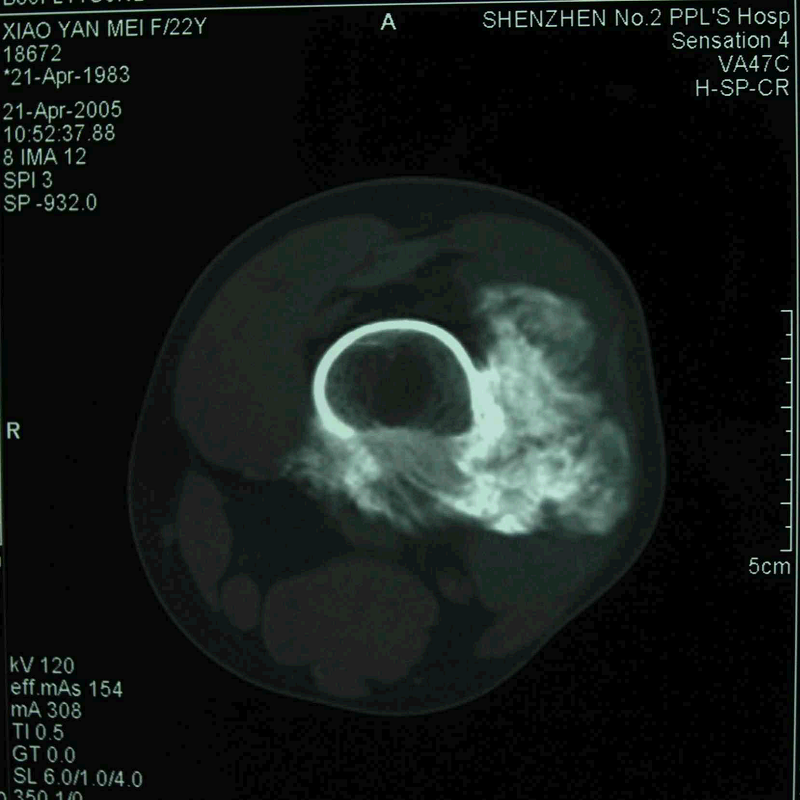

图 14 术前CT

图 15 术前CT三维重建象